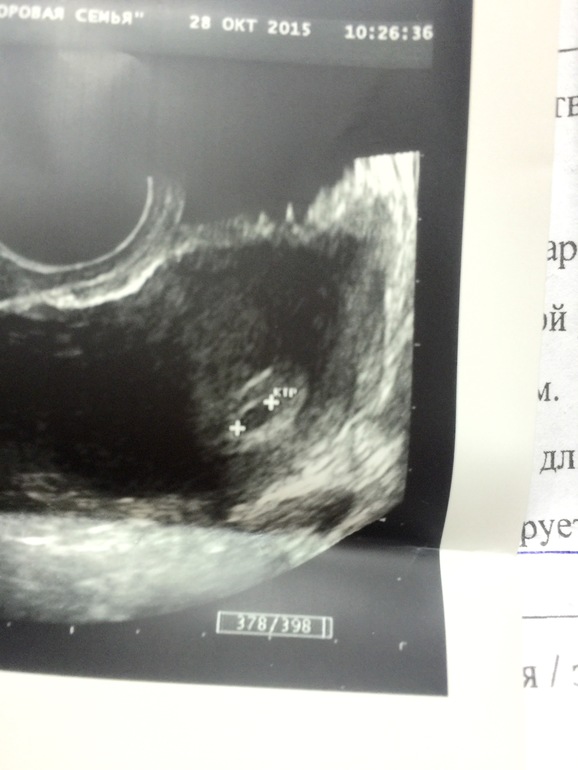

у меня ктр 2 мм был при плодном яйце 8 мм. рано у вас еще эмбрион видеть.